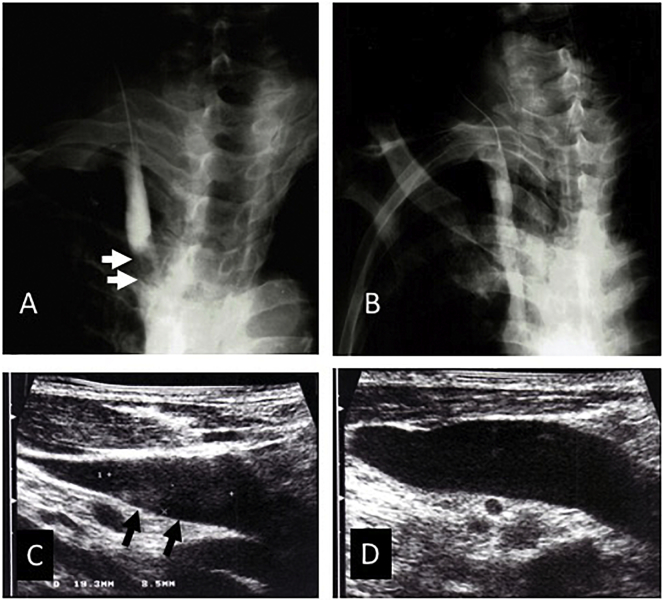

A 71-year-old male was transferred to our facility with disturbance of consciousness (Glasgow Coma Scale; GCS of E3V4M6). Bilateral papilledema was present. The laboratory test revealed anemia and coagulation abnormality (Table 1). Computed tomography (CT) without contrast material and magnetic resonance imaging (MRI) of the brain with and without gadolinium showed no intrusive mass, hydrocephalus, or any other structural lesion. A lumbar puncture showed an opening pressure of 510 mm H2O with normal CSF cell count. This case was diagnosed tentatively as PTC or IIH. On the second day, after being admitted to the hospital, the patient deteriorated to a comatose state (GCS of E1V1M4). Cerebral angiography showed no morphological abnormalities, but it revealed an asymmetric right dominant type of confluence of the sinuses with the partially-communicating left transverse sinus in the venous phase (Fig. 1). Furthermore, there was a delay in the cerebral circulation time (CCT) [5] of 9 s. Subsequently, venography of the right internal jugular vein (IJV) and ultrasonography revealed right internal jugular vein thrombosis (Fig. 2A and C). The patient recovered from the disturbance of consciousness immediately after an emergency ventriculoperitoneal shunt and subsequent anticoagulation therapy using warfarin at a dose of 3 mg/day. IJV venography and ultrasonography showed the resolution and recanalization of the right JVT (Fig. 2B and D).

Fig. 2.

(A) The pre-therapeutic venogram of the right internal jugular vein (IJV), in frontal projection, shows the obstruction of the lower IJV. The arrows indicate the filling defect of the jugular vein thrombosis (JVT). (B) A post-therapeutic venogram obtained after anticoagulation therapy using warfarin shows the resolution and recanalization of the JVT.

(C) A pre-therapeutic ultrasonogram of the right internal jugular vein (IJV) shows the jugular vein thrombosis (JVT). The arrows indicate the thrombus in the right IJV.

(D) A post-therapeutic ultrasonogram after the anticoagulation therapy using warfarin shows the resolution and recanalization of the JVT.